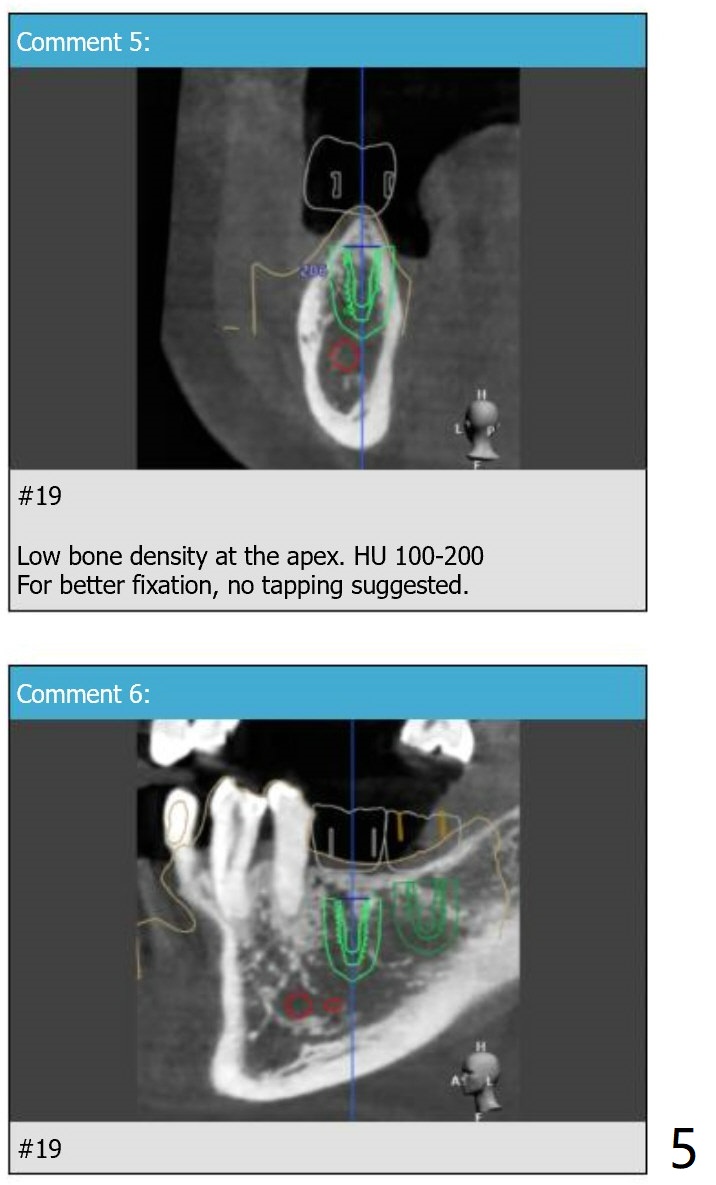

Fixture Anchor Pin at #18

Return to Lower Molar Immediate Implant Armaments  Placement